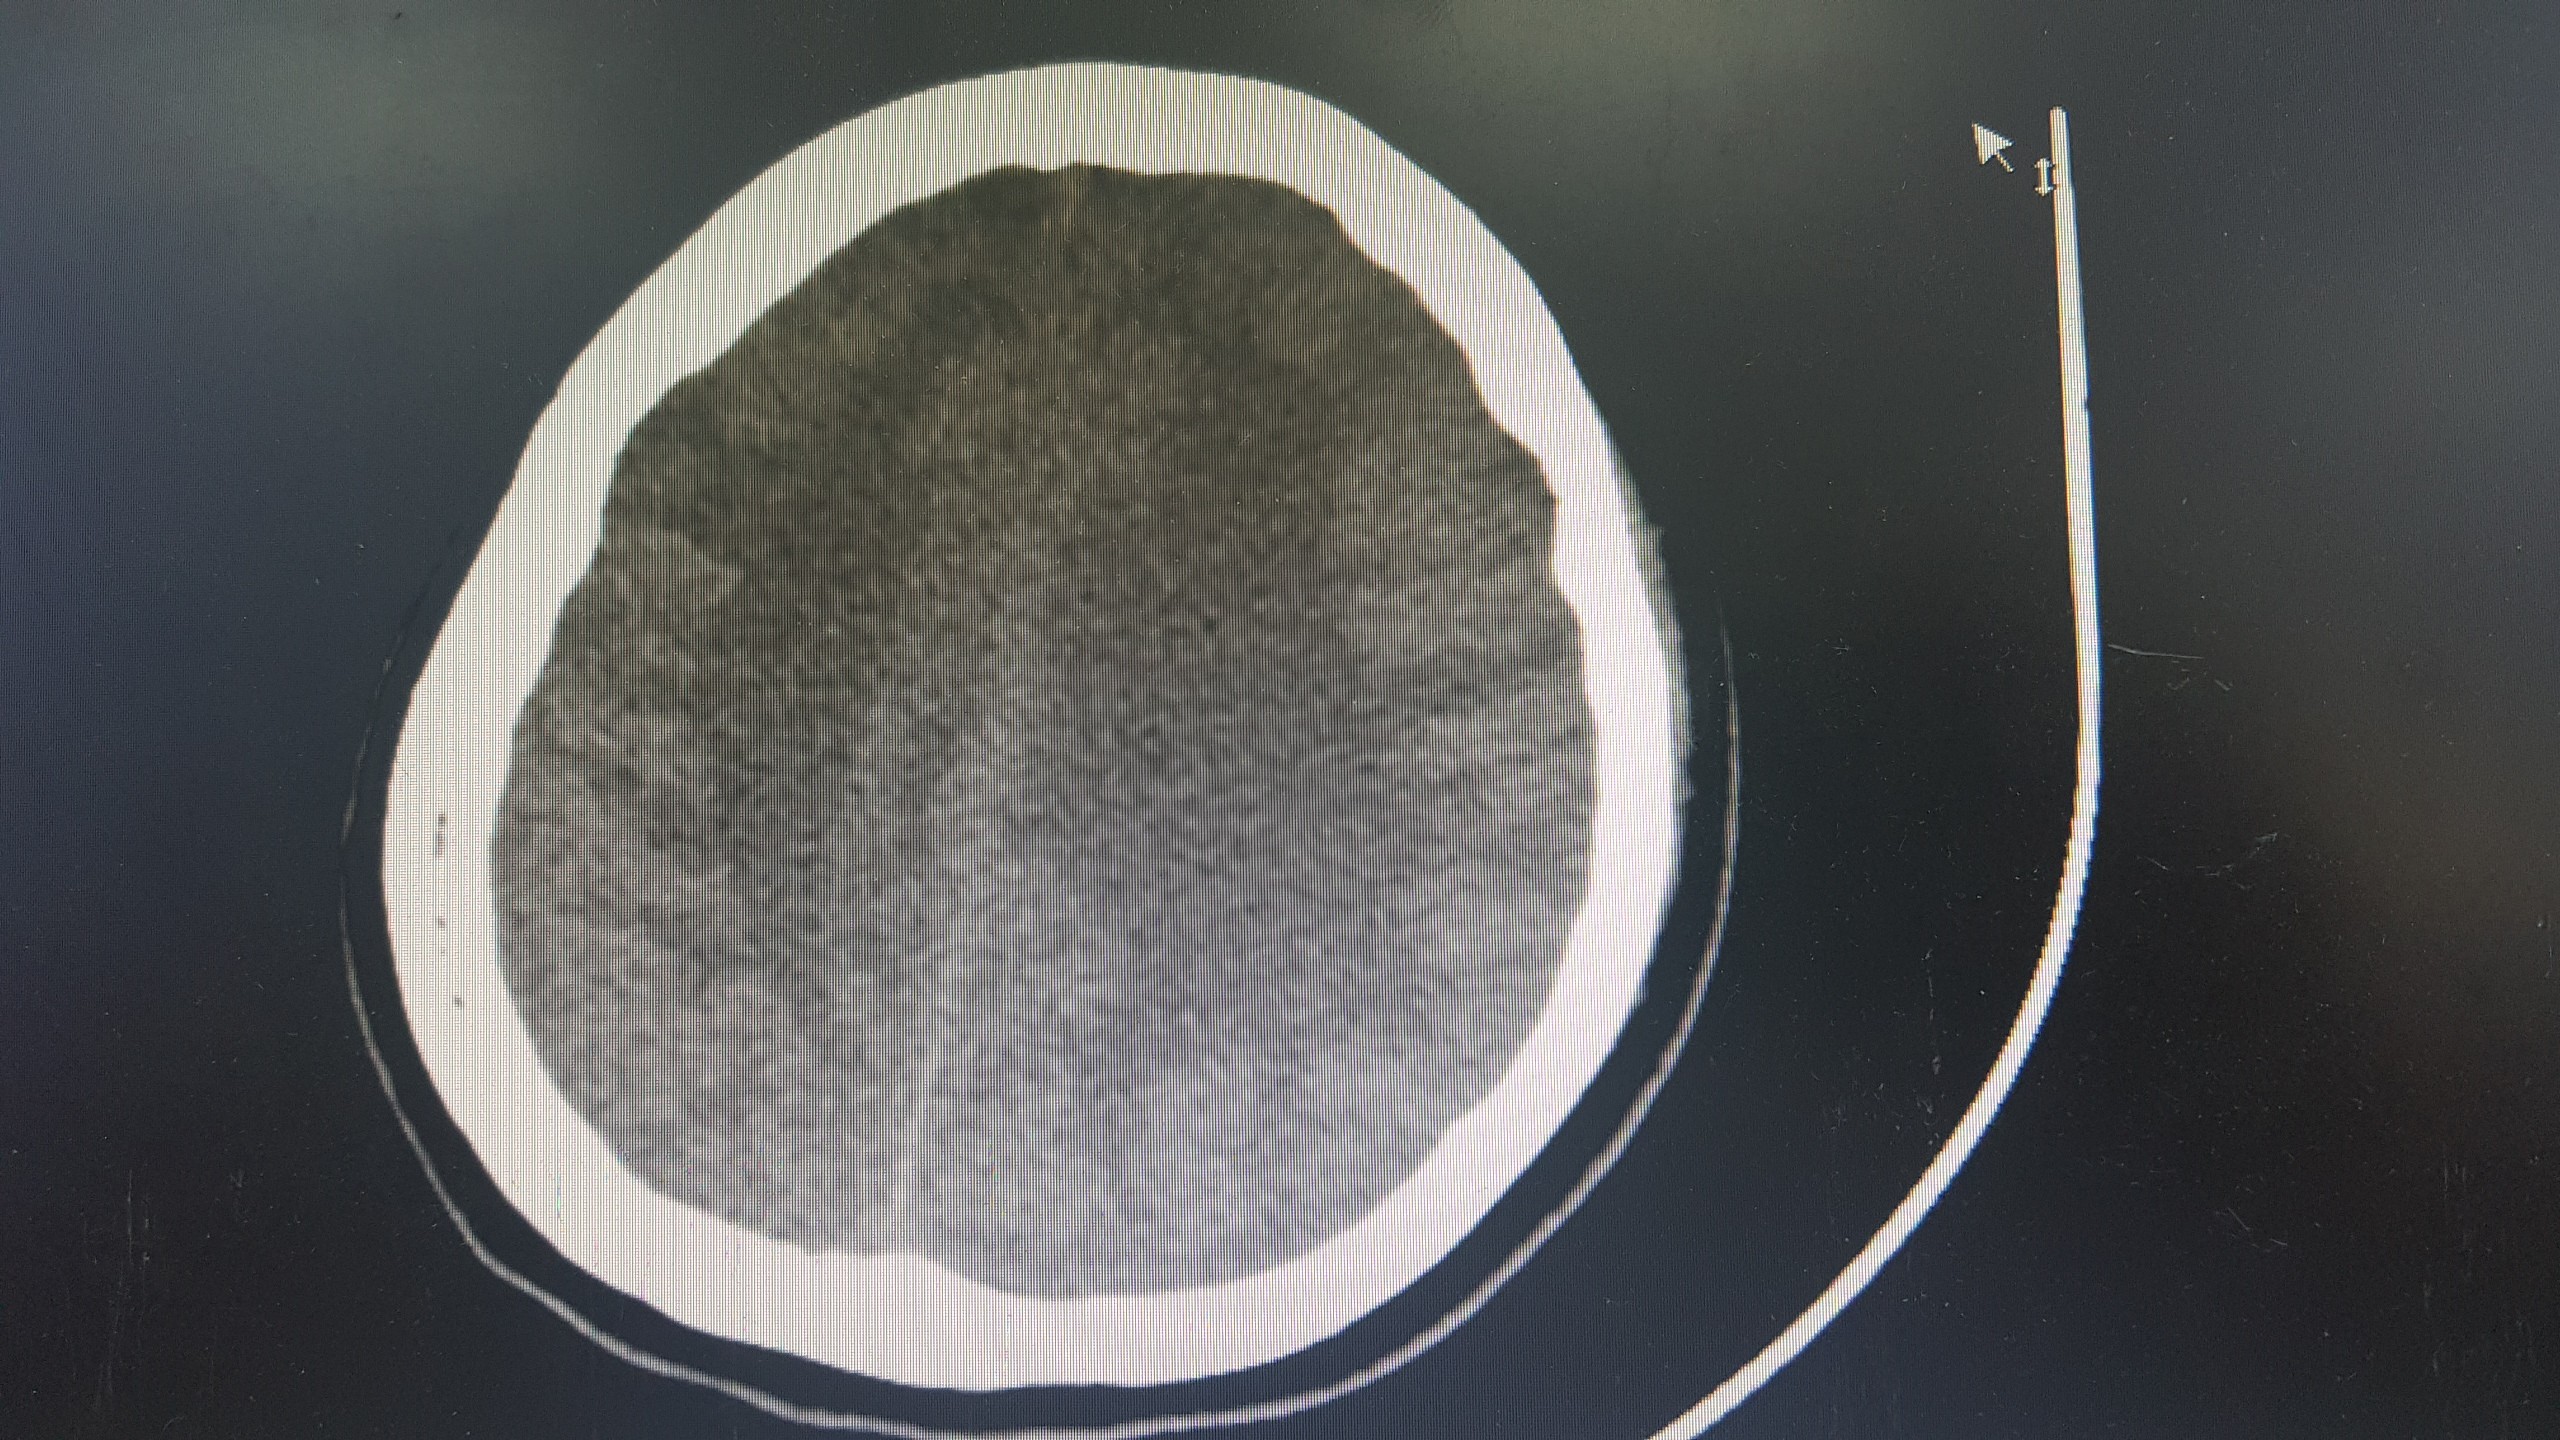

TS.BS. Nguyễn Trung Nguyên, Giám đốc Trung tâm Chống độc, Bệnh viện Bạch Mai cho biết: Bệnh nhân đang trong tình trạng rất nguy kịch do tổn thương và suy nhiều cơ quan, trong đó nặng nhất là tổn thương não lan tỏa tại tất cả các vị trí. Trường hợp của bệnh nhân gần giống như ca đột quỵ não nhưng nặng hơn rất nhiều. Nếu đột quỵ não chỉ gây tổn thương nhỏ ở một số vị trí thì ở trường hợp này là tổn thương gần như toàn bộ não. Ngoài ra, bệnh nhân còn bị tổn thương và suy tim nặng, suy thận, tổn thương gan. Tiên lượng điều trị và hồi phục của bệnh nhân là vô cùng dè dặt.

Ảnh chụp não bị tổn thương của bệnh nhân